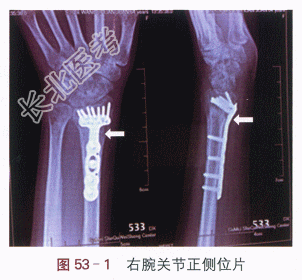

X线片提示:右侧桡骨远端骨折内固定术后,如图53-1所示。